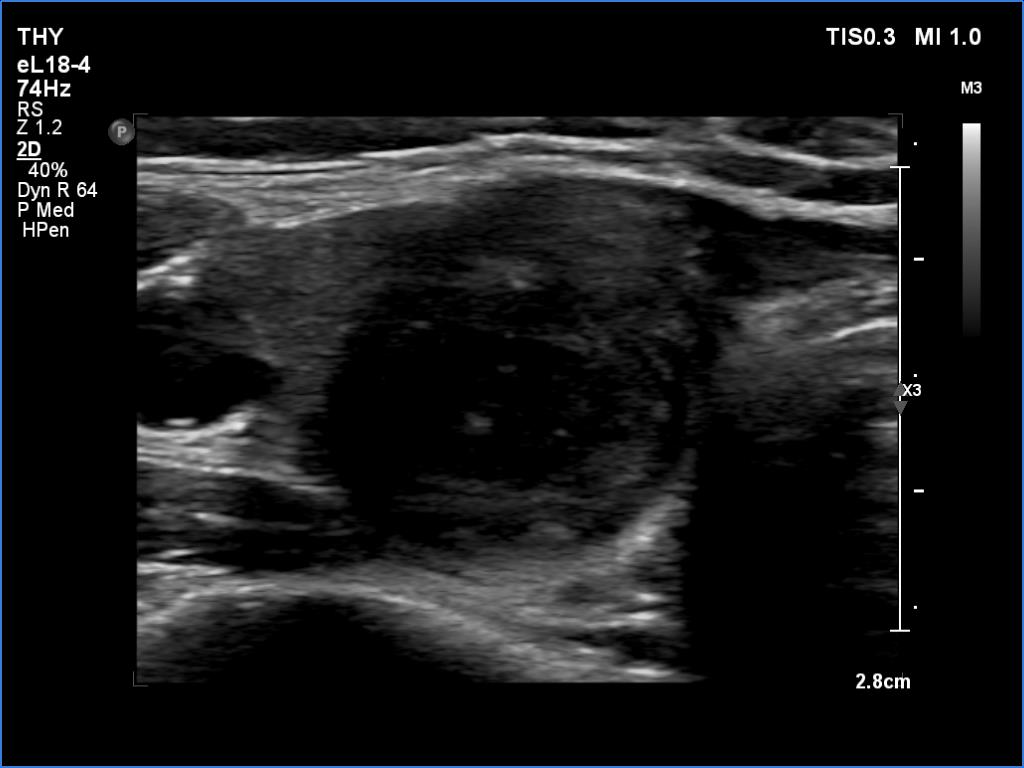

Ultrasonography revealed an echonormal thyroid. There was dominantly moderately hypoechoic nodule in the right lobe. Some parts of the lesion were deeply hypoechoic, and a few small cystic chambers were also within. The nodule presented with irregular shape and borders and had intranodular echogenic figures, primarily granules.

It is ambiguous how to interpret the echogenic figures. Although the presence of irregular shape and borders increases the likelihood that the echogenic granules are indeed microcalcifications, comet-tail artifacts must be also considered.

It is worth comparing the images recorded by using different settings. By using harmonization, we lose the details of very hypoechoic areas. Essentially, the latter seem to be anechoic.